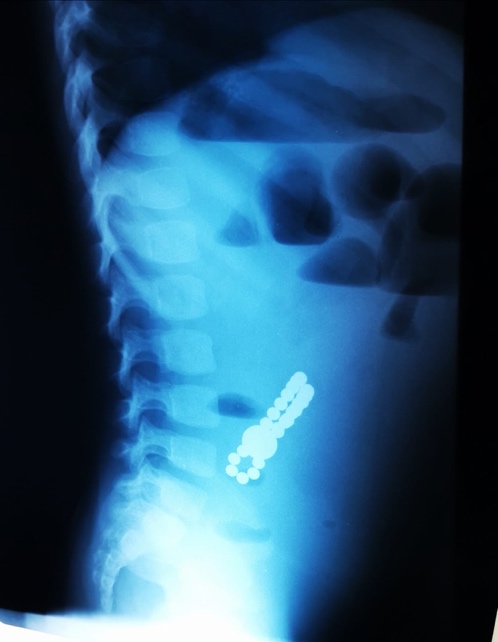

FOTO Periculos! Peste 250 de copii din județul Botoșani au ajuns la spital după ce au înghițit mărgele, baterii, șuruburi sau magneți. Avertismentul unui medic